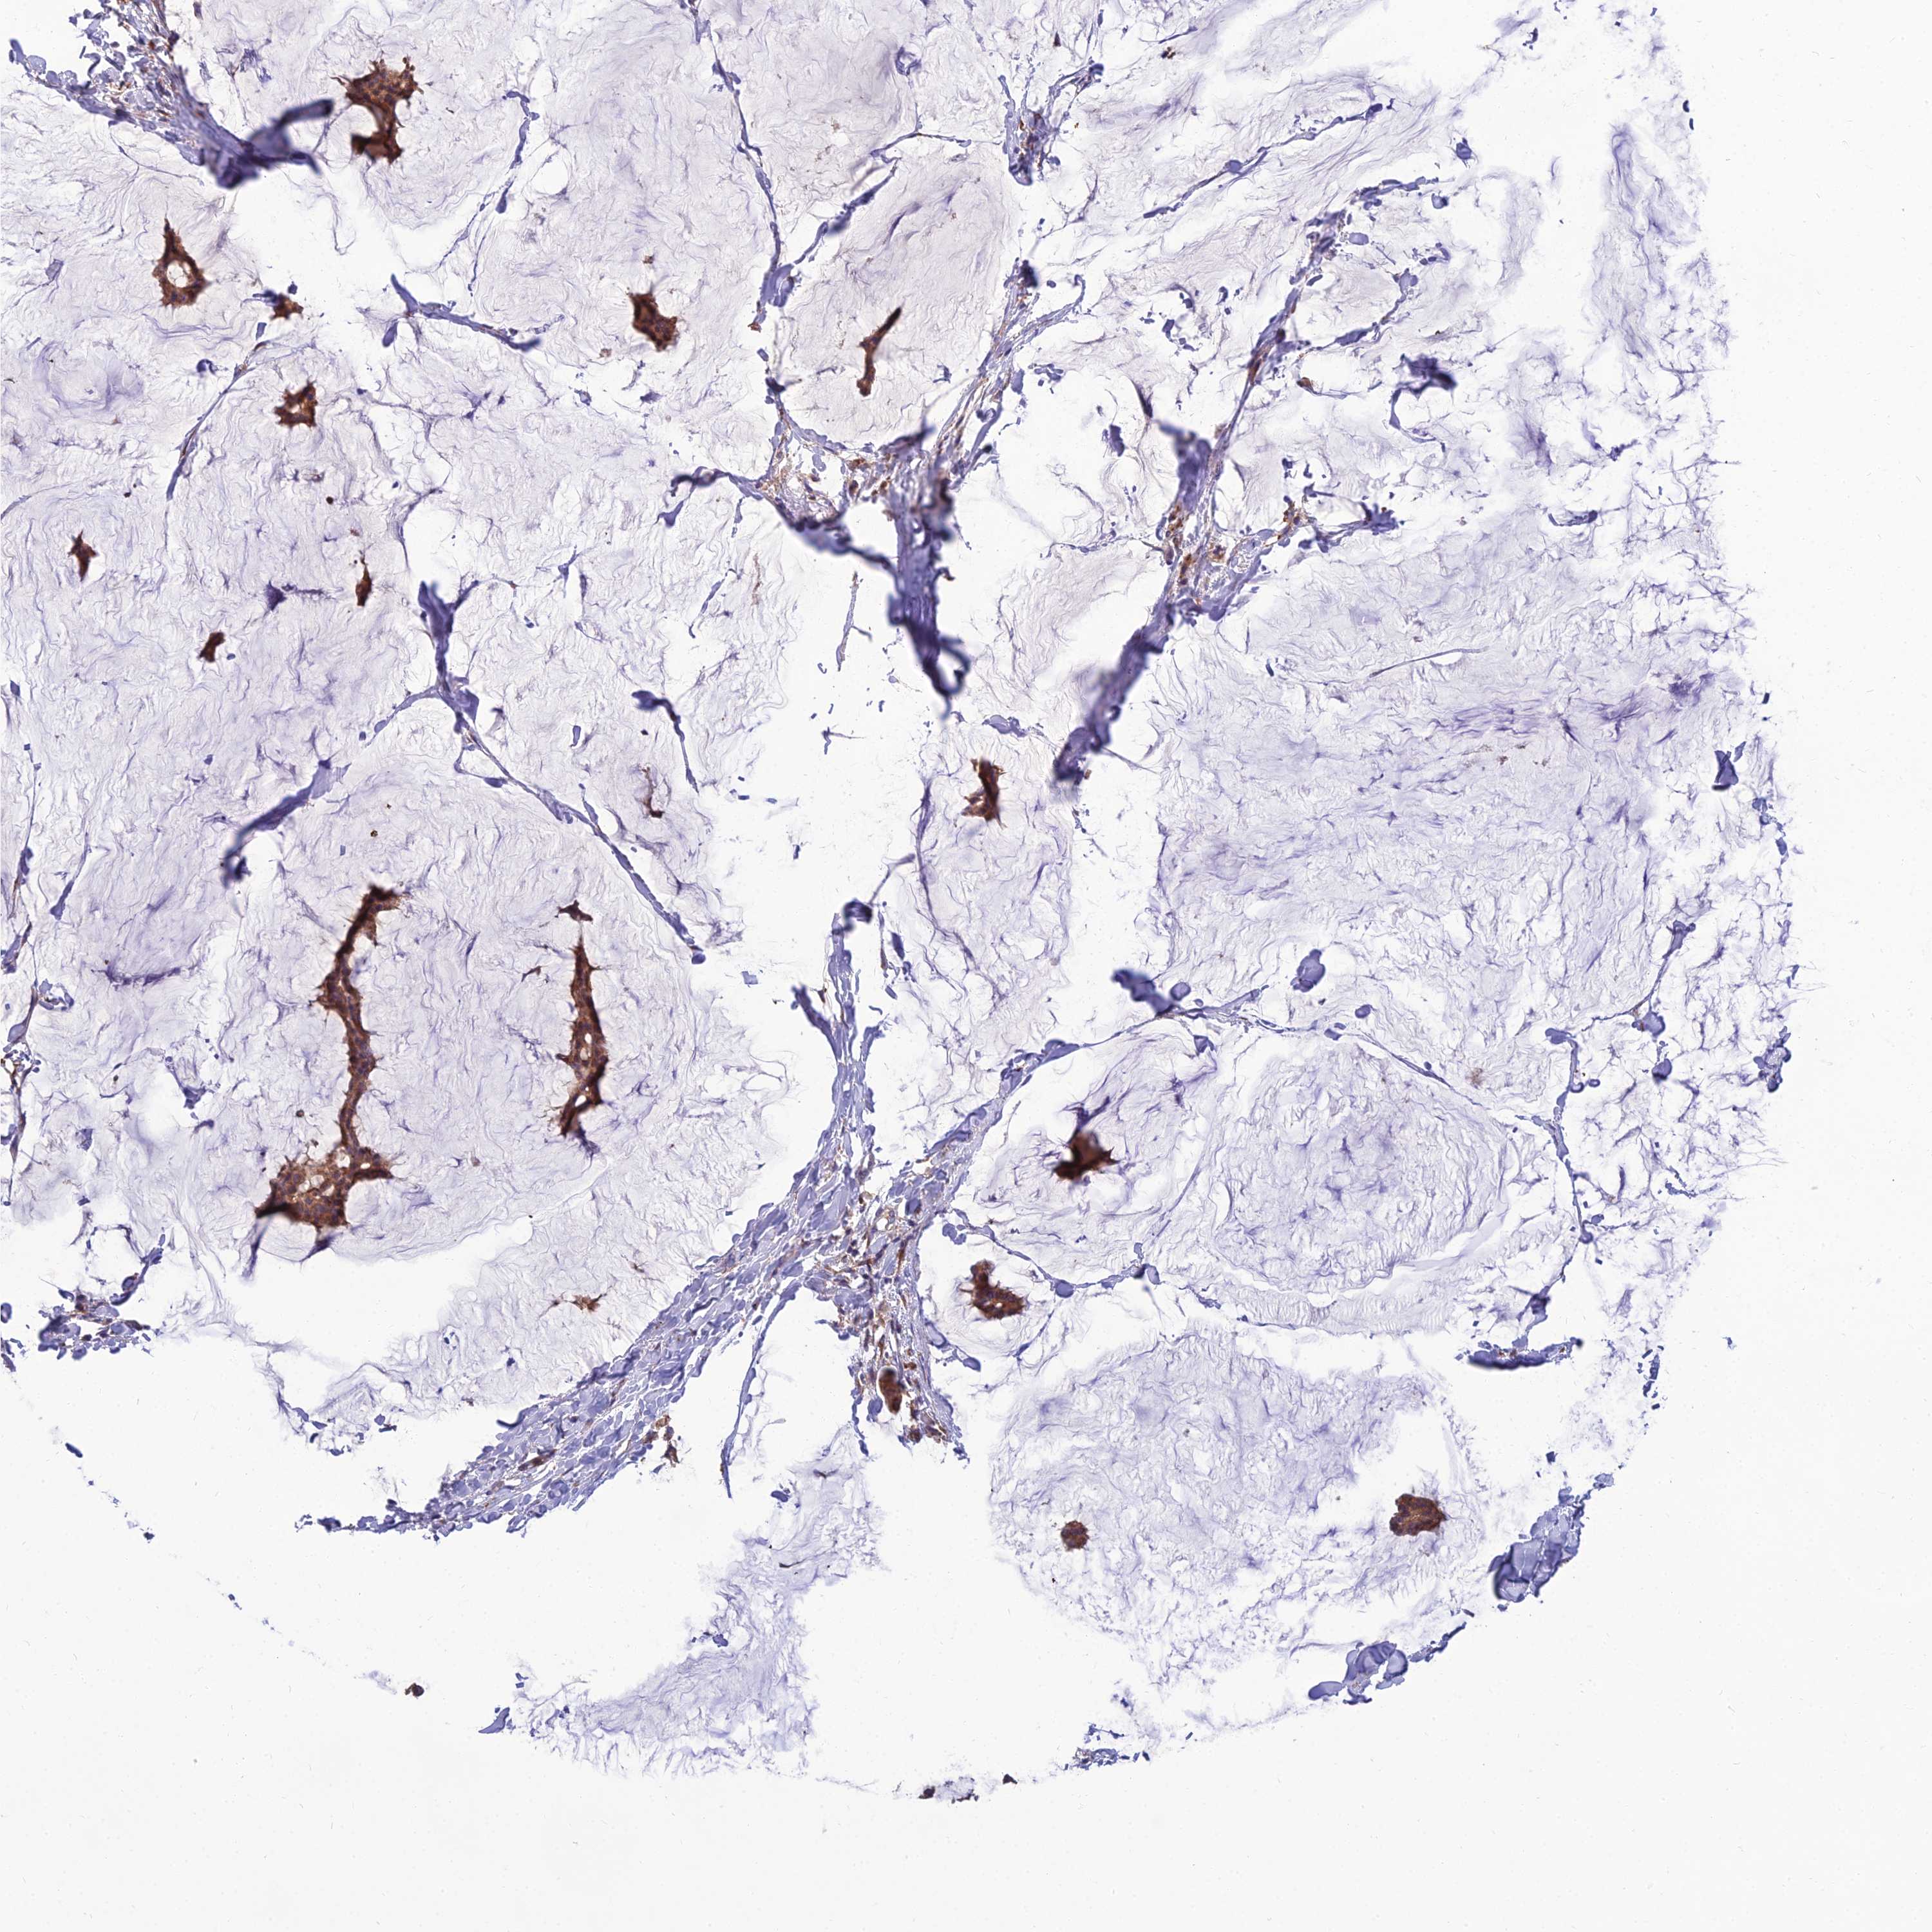

BRCA TCGA BRCA VALIDATION PROTEIN EXPRESSION

ANTIBODIES

AND

VALIDATION